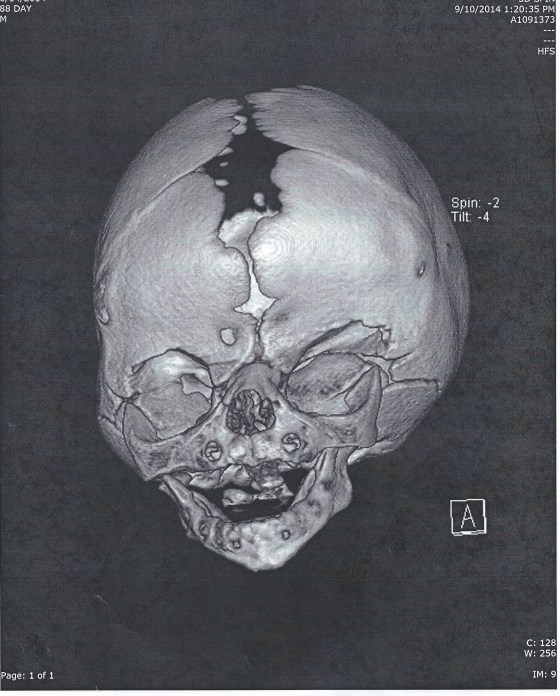

The Craniofacial department has a camera that takes a 3D picture. These next two pictures show a comparison of Isaac’s head from the beginning of May, before his last surgery. The pictures on the right are from May and the pictures on the left are from a few weeks ago. You can really tell a difference in the shape of his head.